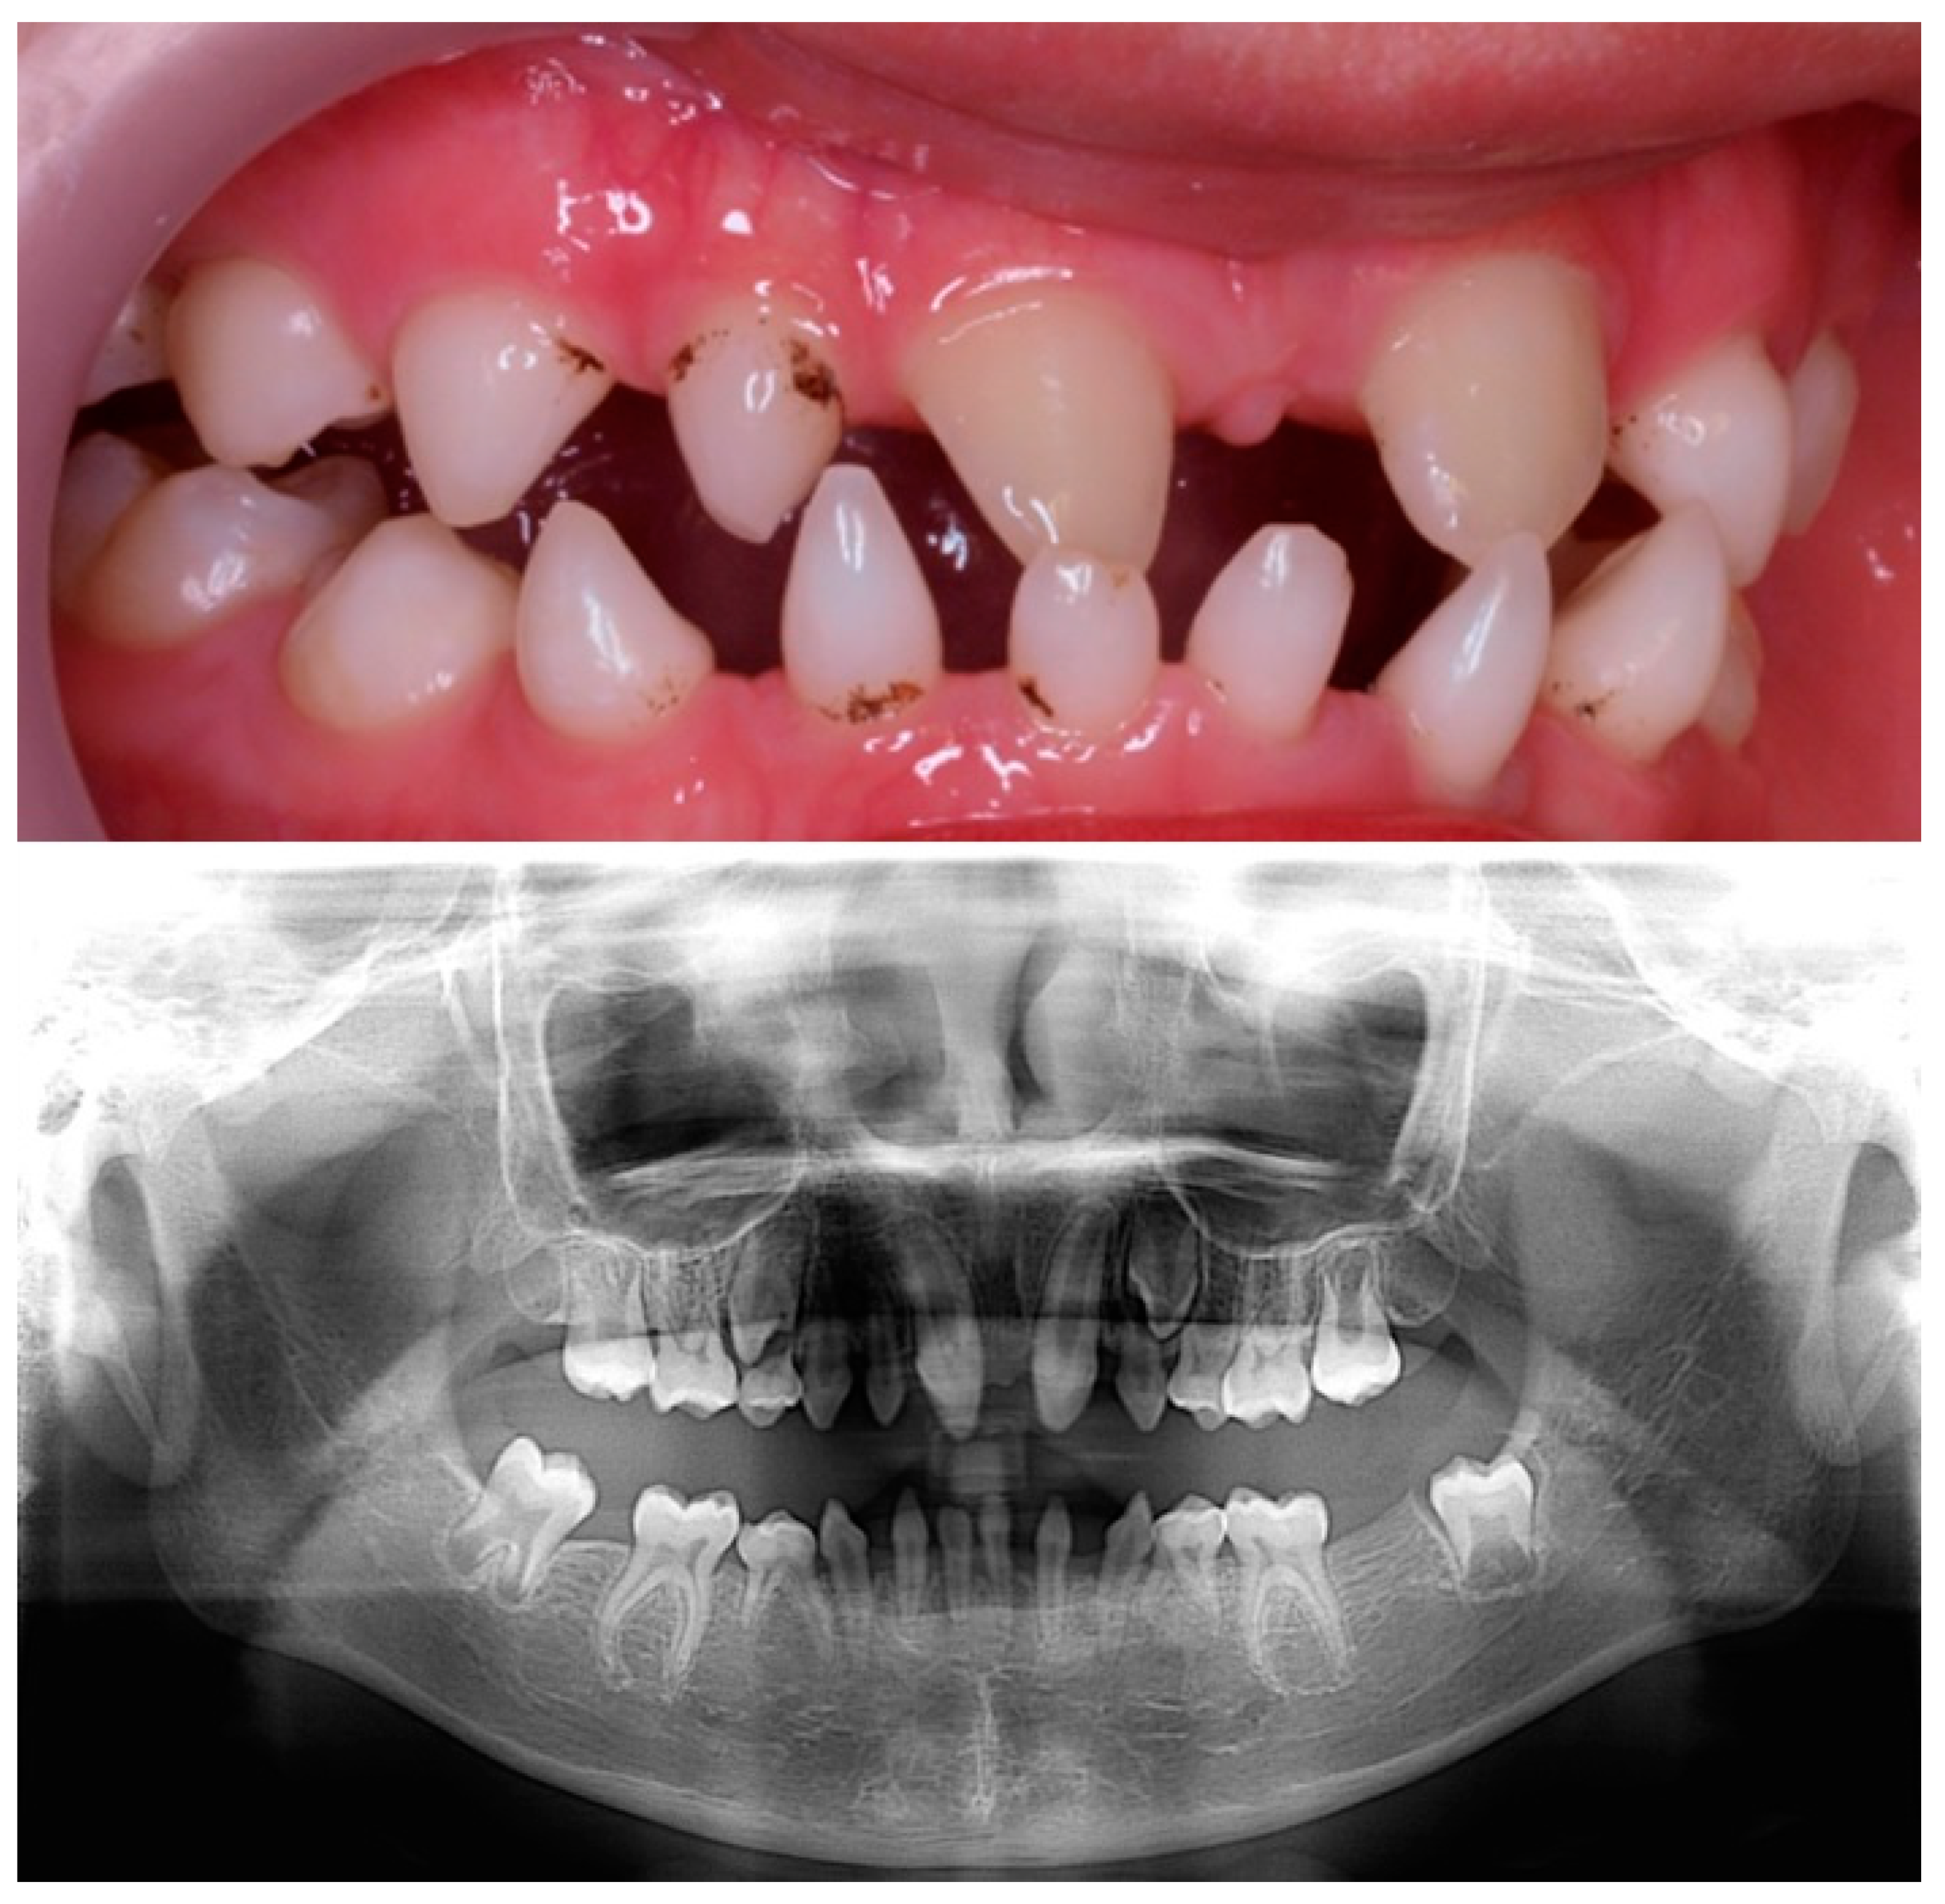

Figure 3.

Clinical and radiographical findings at 11 years old.

The child was followed up by the dentist. At present, the patient is 11 years old with normal psychomotor development, and his dental phenotype showed two conical maxillary central incisors and the first permanent molars. There were still conical-shaped anterior primary teeth and first primary molars. The germs of the second permanent molars were visible (Figure 3). The patient was then monitored by the dentist for treatment planning to address the growth and development of the jaws and subsequent rehabilitative treatment.